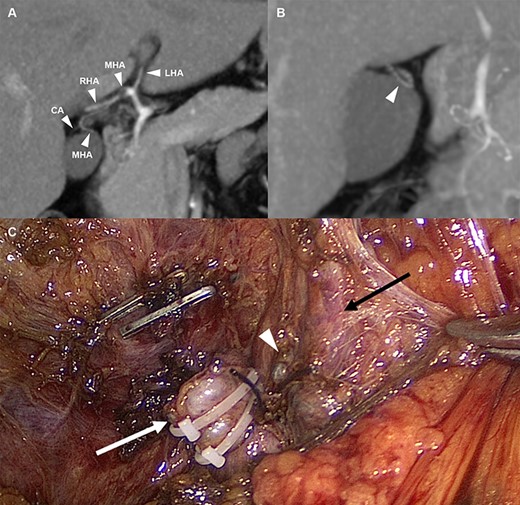

A 42-year-old man visited the outpatient department complaining of chronic epigastric pain for the past 1 year, without surgical or medical history. The frequency and severity of epigastric pain had increased since 6 months. Ultrasonography revealed gallbladder wall thickening with stones, indicating chronic cholecystitis, and it was decided to perform laparoscopic cholecystectomy. During the preoperative evaluation, an interesting finding was observed on computed tomography. The patient had a cystic artery arising from the MHA (Fig. 1A). An MHA derived from the hilum of the proper hepatic artery runs along the medial border of the gallbladder and enters segment IV (Fig. 1B).

(A) Arterial anatomy; the MHA derived from the hilum of the hepatic artery and the CA arising from the MHA (B) The MHA that runs into segment IV (C) Anatomical structures after cholecystectomy; white arrow: cystic duct stump, white wedge: CA stump, and black arrow: MHA. LHA, left hepatic artery; MHA, middle hepatic artery; RHA, right hepatic artery; CA, cystic artery.

Keeping in mind this anatomical variation, laparoscopic cholecystectomy was performed. Moderate adhesion around Calot’s triangle was observed due to previous colic attacks. The omentum, round ligament and gallbladder were adhered to each other, and it was difficult to separate each of them. After careful dissection of the medial border of the gallbladder, the MHA that ran to segment IV was observed. Dissecting downward along the MHA, a cystic artery was observed around the cystic duct. The cystic artery and duct were isolated and each was separately ligated and cut. The gallbladder was detached from the liver and hemostasis was achieved. After insertion of a drainage catheter into the subhepatic space, abdominal closure was performed. The patient was discharged on postoperative Day 5 without any adverse events.